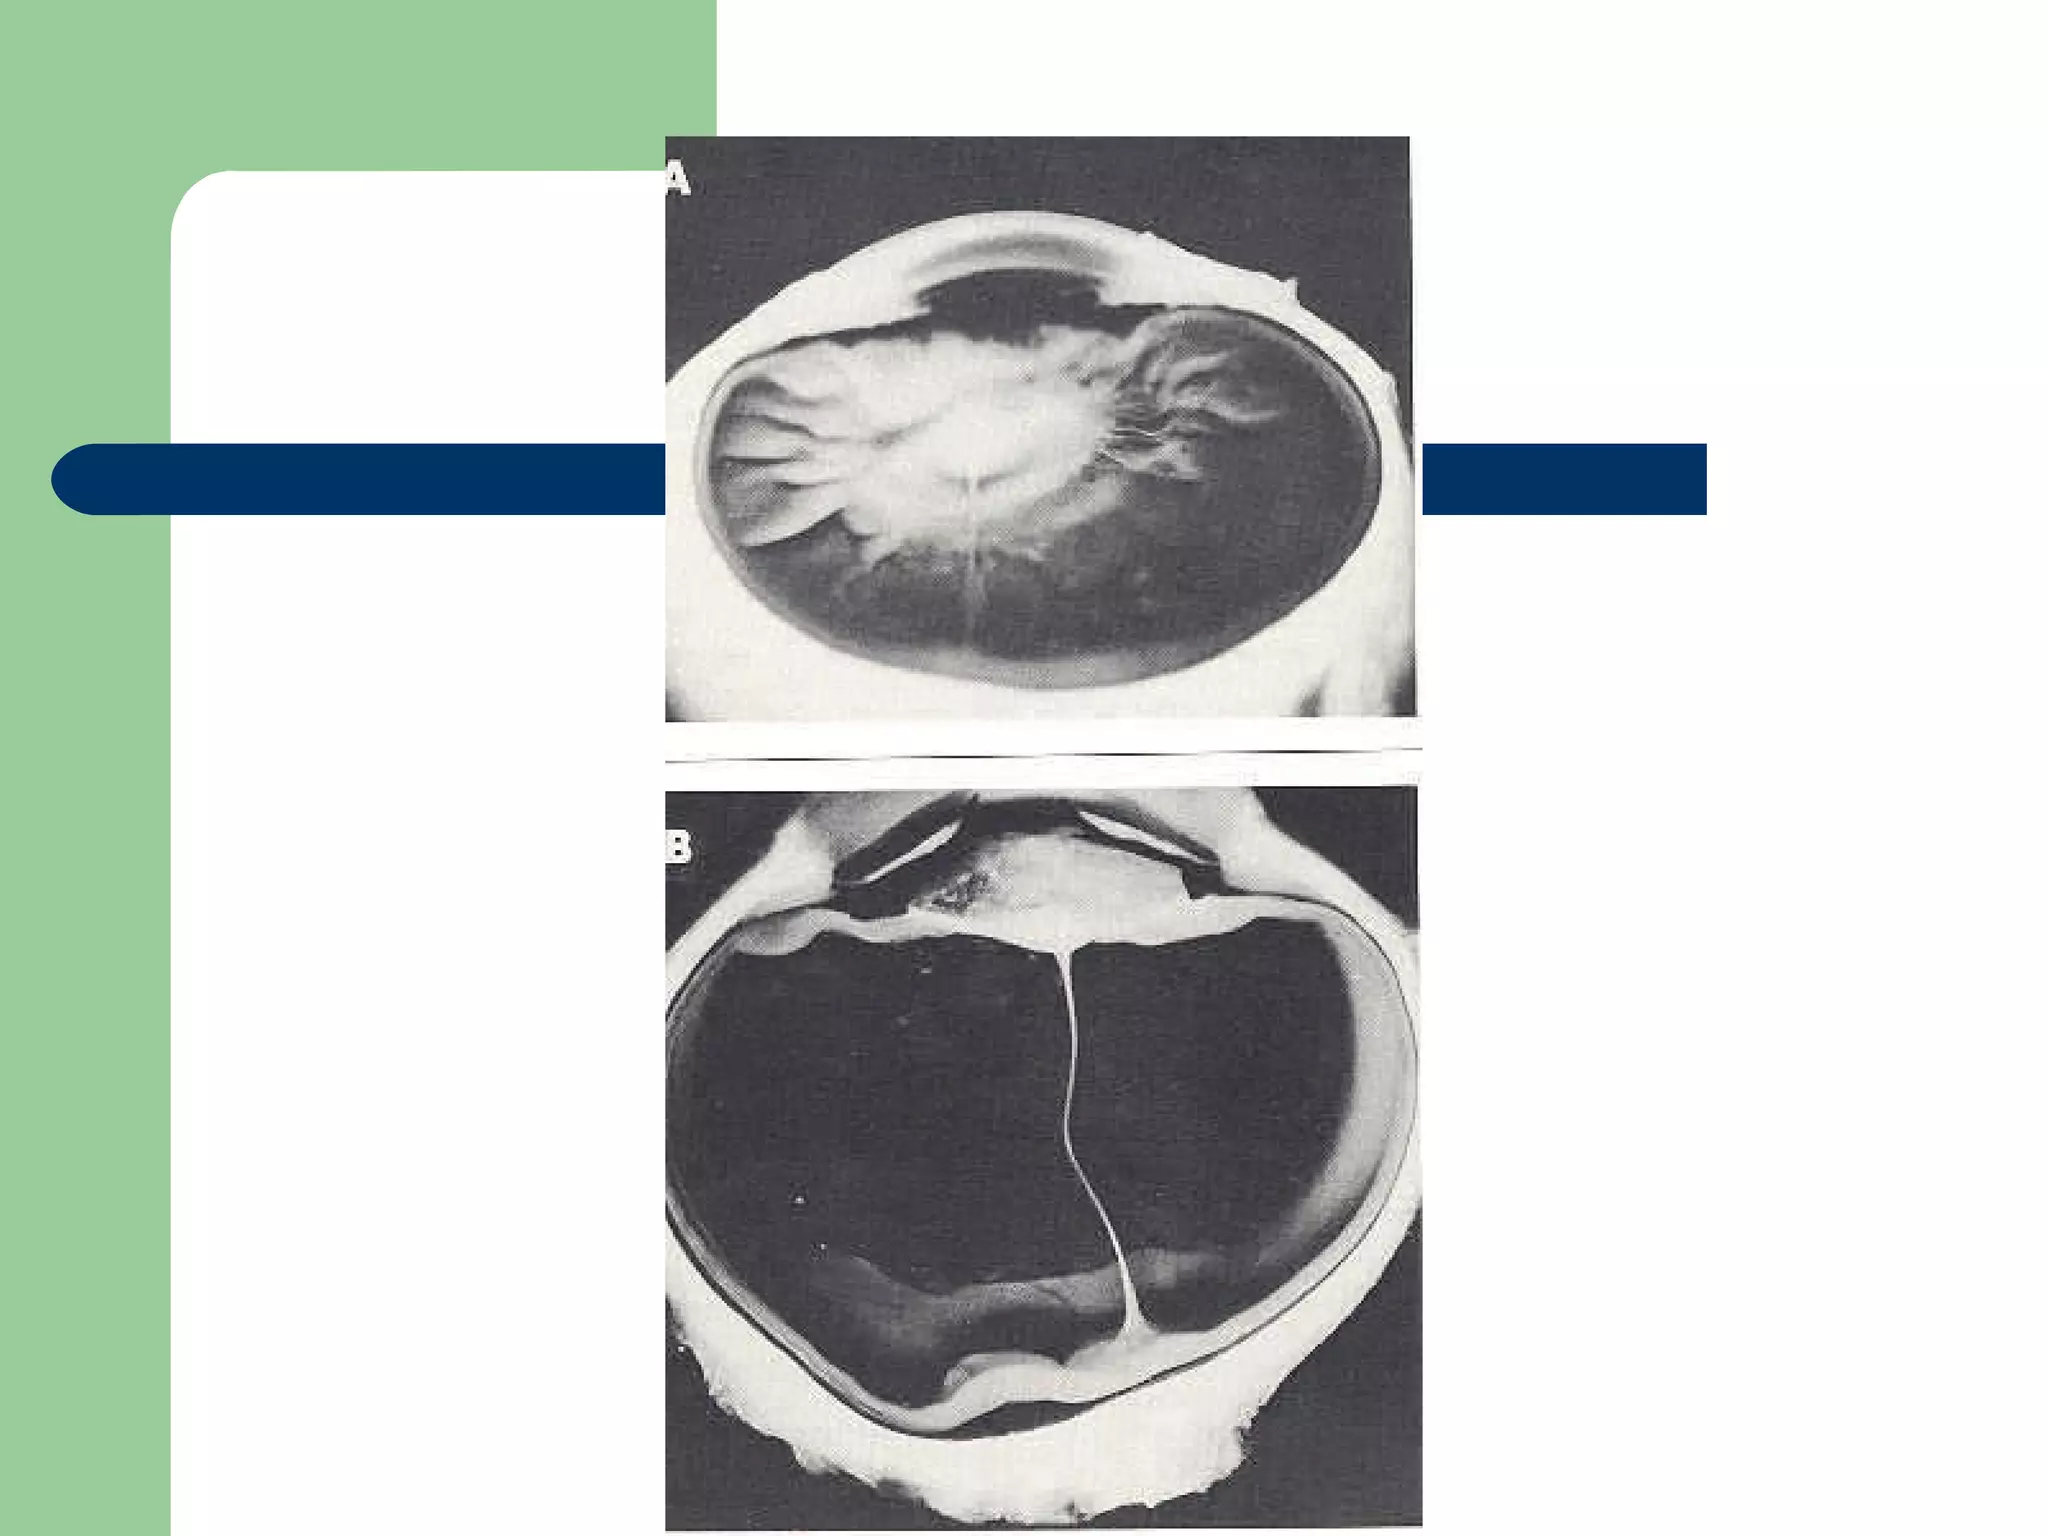

Persistent hyperplastic primary vitreous

Retrolental fibroplasia Temporal retinal traction  Paton et al - Introduction to ophthalmoscopy

• #66 Enfermedad de bebes prematuros expuestos a oxigeno suplementario. Causa vasoconstricción de y oclusión de las arterias y mas tarde una reacción de proliferación de vasos sanguíneos y reacción glial asociada causando cicatrización y tracción de la retina. Como los vasos temporales son os mas inmaduros en el nacimiento, son los mas afectados y halan la macula temporalmente